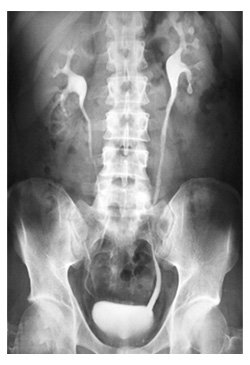

Este examen generalmente se realiza en pacientes ambulatorios. Usted yacerá sobre la mesa y se toman imágenes estáticas de rayos X. Luego se inyecta el medio de contraste, generalmente en la vena de su brazo, y se toman imágenes estáticas adicionales. El número de imágenes tomadas depende de su anatomía y del motivo por el que se realiza el examen. Usted debe permanecer inmóvil y se le puede solicitar que contenga la respiración por unos segundos mientras se toma la imagen de rayos X para reducir la posibilidad de que ésta resulte borrosa. El tecnólogo se dirigirá detrás de una pared o hacia la sala contigua para activar la máquina de rayos X.

Mientras el medio de contraste es procesado por los riñones, se toman una serie de imágenes para determinar el tamaño real de los riñones, y para tomar imágenes del tracto urinario en funcionamiento a medida que se vacía. El tecnólogo puede aplicar una banda de compresión alrededor del cuerpo para visualizar mejor las estructuras urinarias. Al completar el examen, se le podría pedir que espere hasta que el tecnólogo determine que se hayan obtenido todas las imágenes necesarias.

Pielograma descendente:

Una pielografía descendente es un estudio de diagnóstico por imágenes (imagenológico) para detectar bloqueos (obstrucciones) en las vías urinarias superiores. Sus vías urinarias incluyen los riñones, los uréteres y la vejiga. Los uréteres son los conductos angostos que llevan la orina desde los riñones hasta la vejiga.